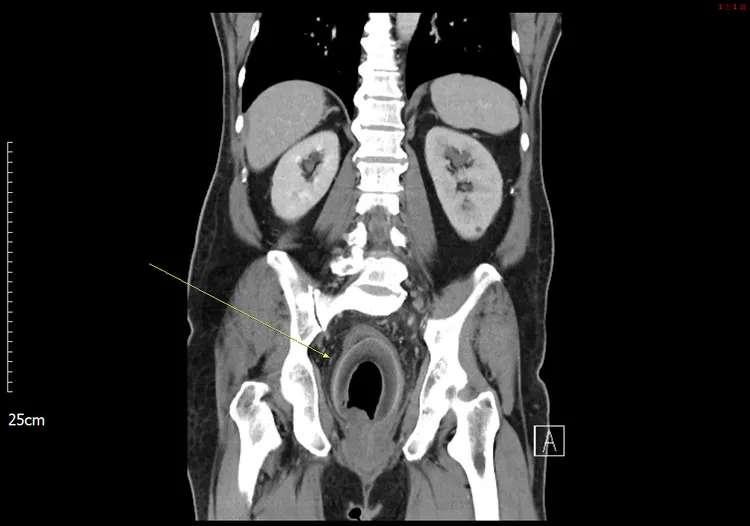

義大醫院表示,這名 56 歲男性患者,主訴腹痛 2 天,伴有無尿和嚴重便秘,但無其他症狀,如發燒、噁心或嘔吐。

院方體格檢查患者生命體徵穩定。腹部檢查發現,腹部膨脹、壓痛,有反彈痛。影像學檢查腹部電腦斷層掃描 (CT) 顯示,直腸內有一個巨大的異物,壓迫前列腺尿道,導致尿滯留。治療患者接受了探查性剖腹手術,從直腸中取出一個「椰子」,實際大小為7.5X5.7X5.5 公分。大腸直腸外科主治醫師陳致一寫成報告,向國際醫學期刊投稿,2023年1月刊登在英國外科雜誌 110 卷第一期,頁碼 123。